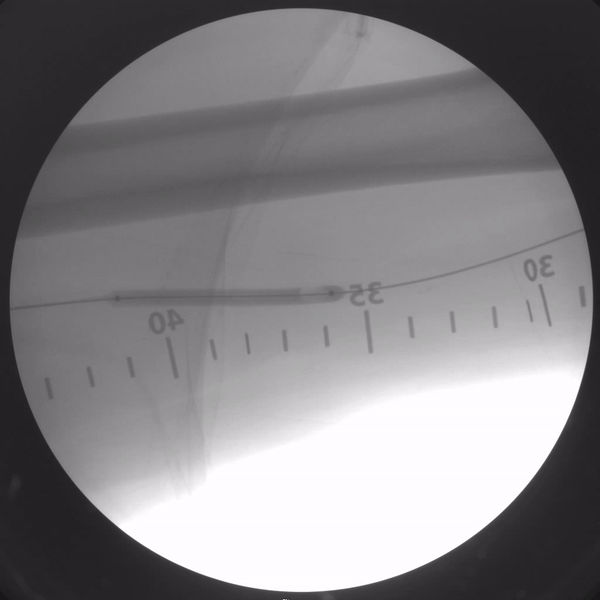

Skan-C provides 45 degree over rotation (over scan) that is particularly helpful for pain management applications. Skan-C is designed to be user-friendly, with an intuitive interface that allows doctors to quickly and easily adjust settings and customize imaging parameters.